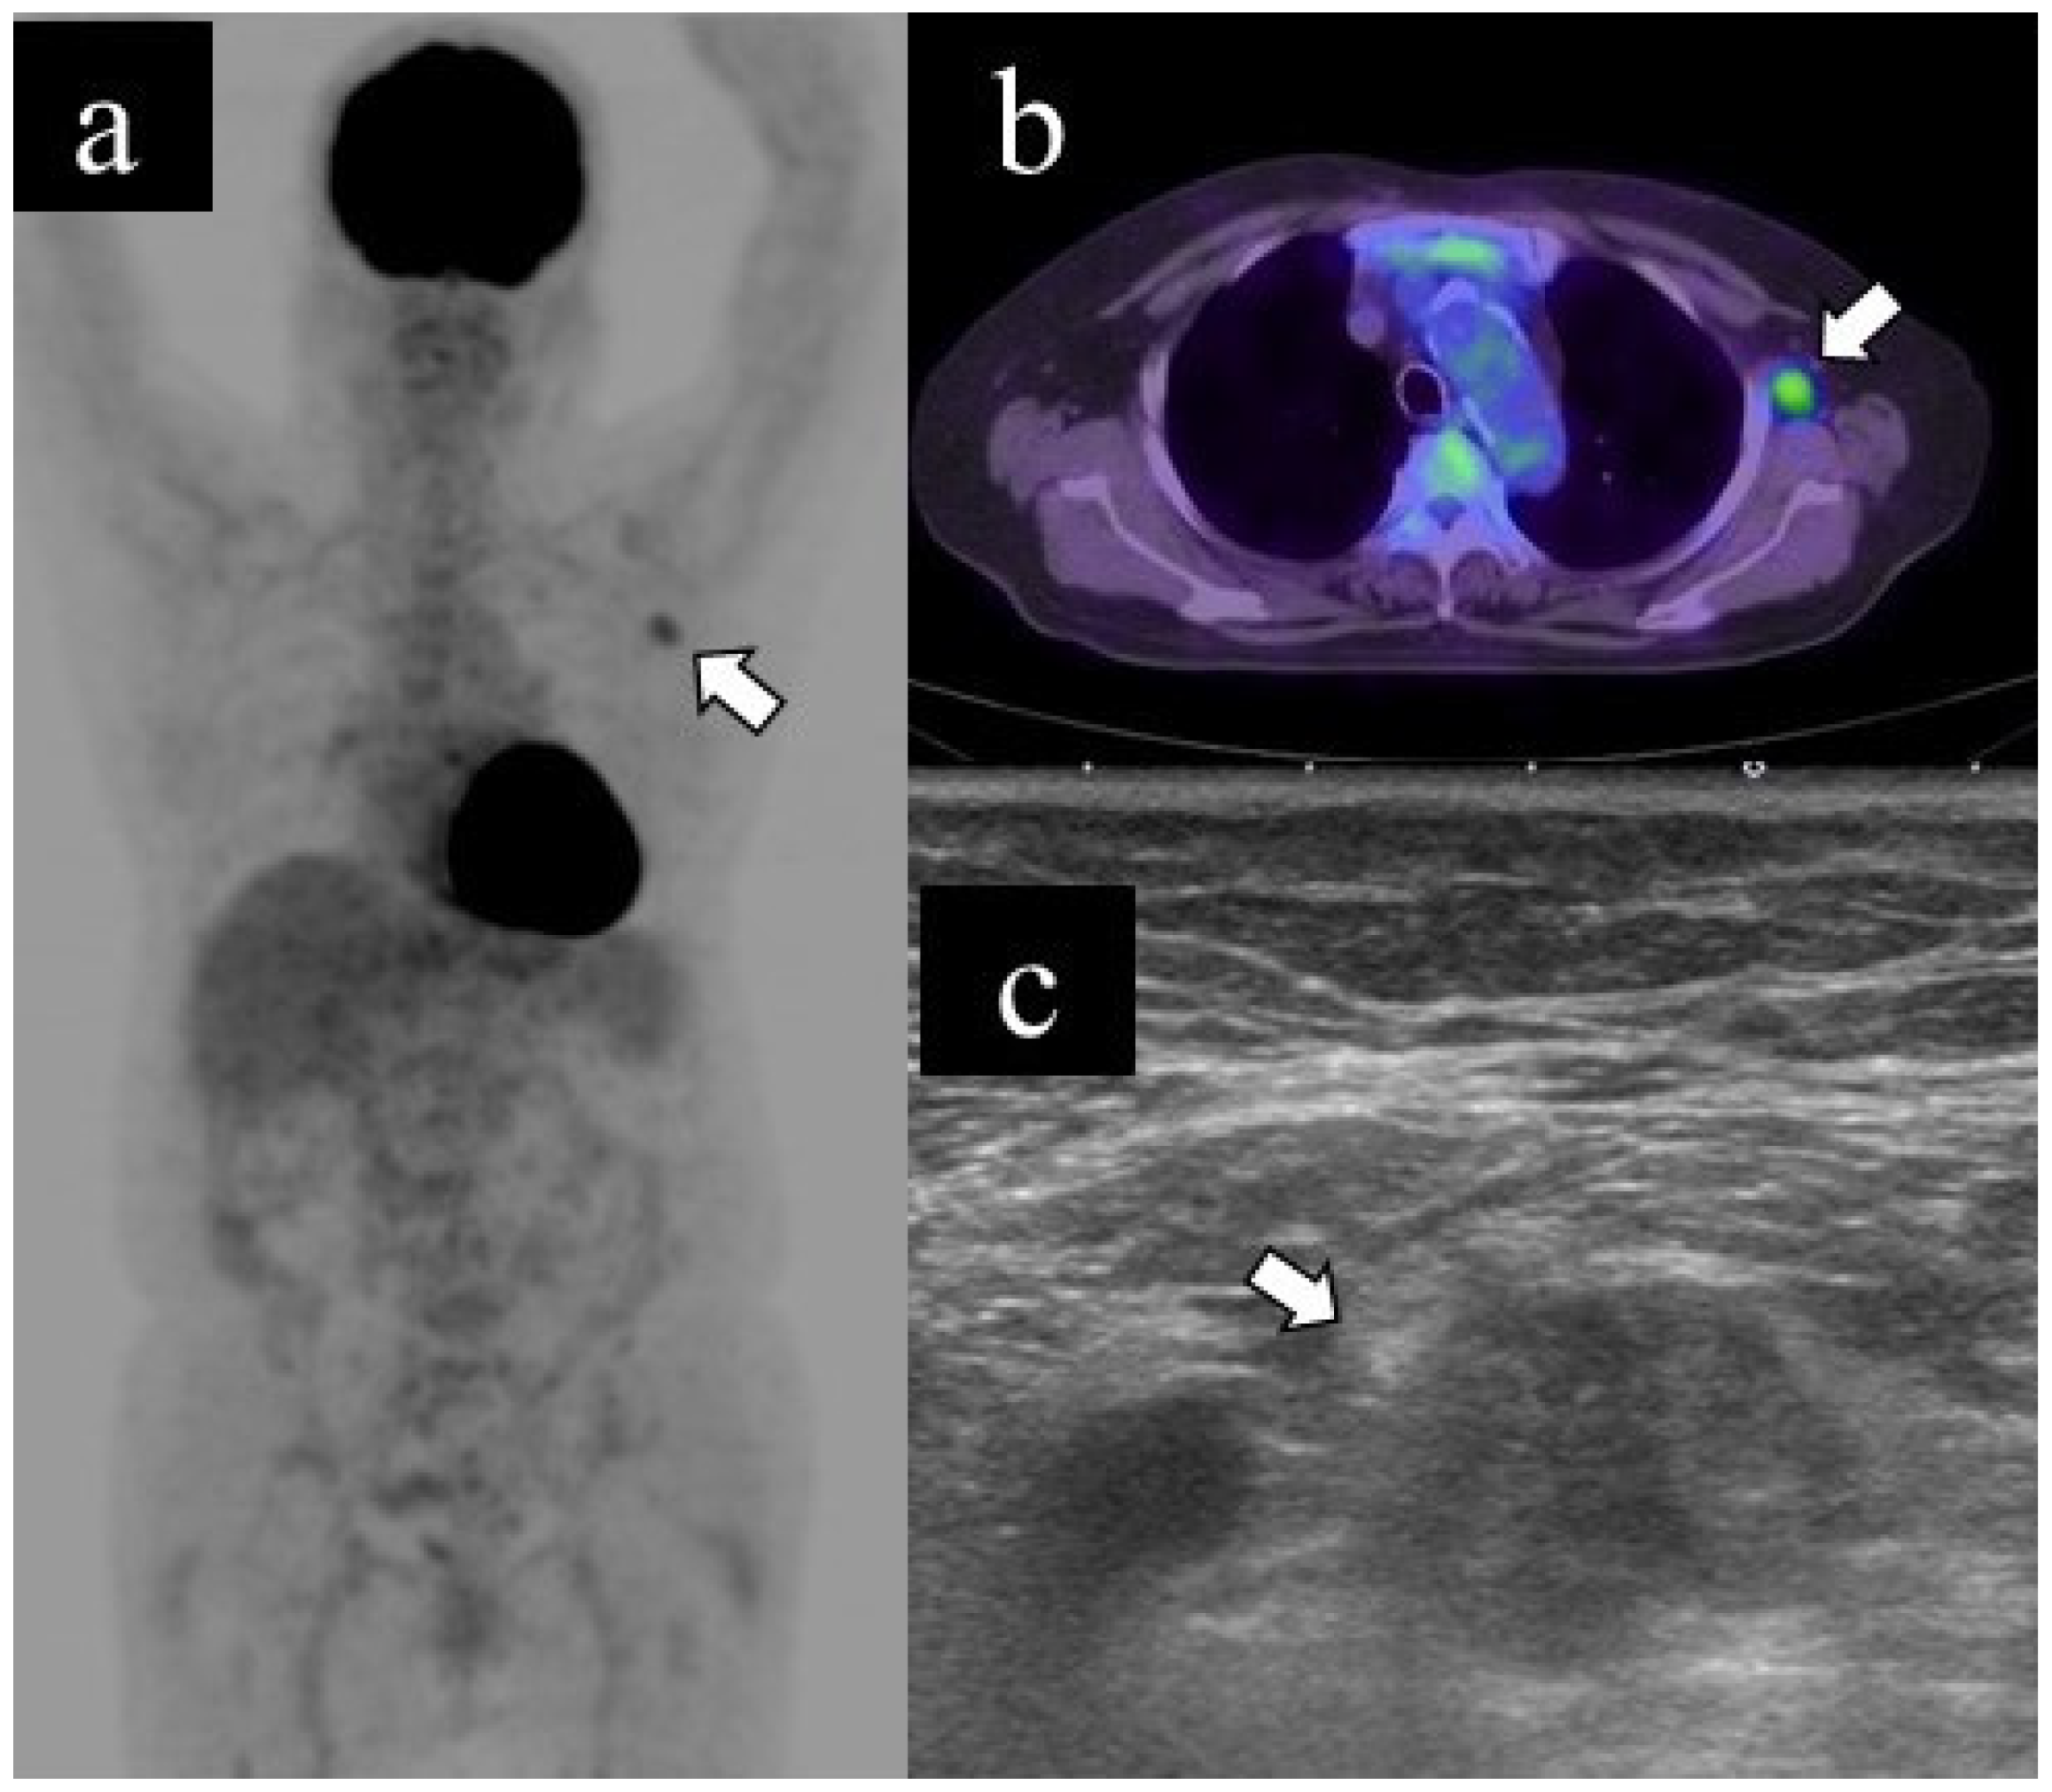

Figure 2 and Figure 3 show representative cases of benign and malignant lymphadenopathy, respectively.

The patient, in her 70s, underwent a PET scan for follow-up after renal carcinoma surgery, which revealed an unexpected abnormal uptake in the left axillary lymph node (a. b). US examination revealed lymphadenopathy (long diameter: 21.8 mm, short diameter: 13.1 mm, cortical thickness: 13.1 mm, loss of fatty hilum) (c); subsequently, she underwent US-guided FNA. The cytological classification was class V. The patient underwent axillary lymph node dissection and was finally diagnosed with axillary lymph node metastasis of renal carcinoma.

Figure 3. Representative case of malignant lymphadenopathy. (a) Maximum-intensity projection (MIP), (b) transaxial 18F-FDG PET/CT image and (c) US image of malignant lymphadenopathy.